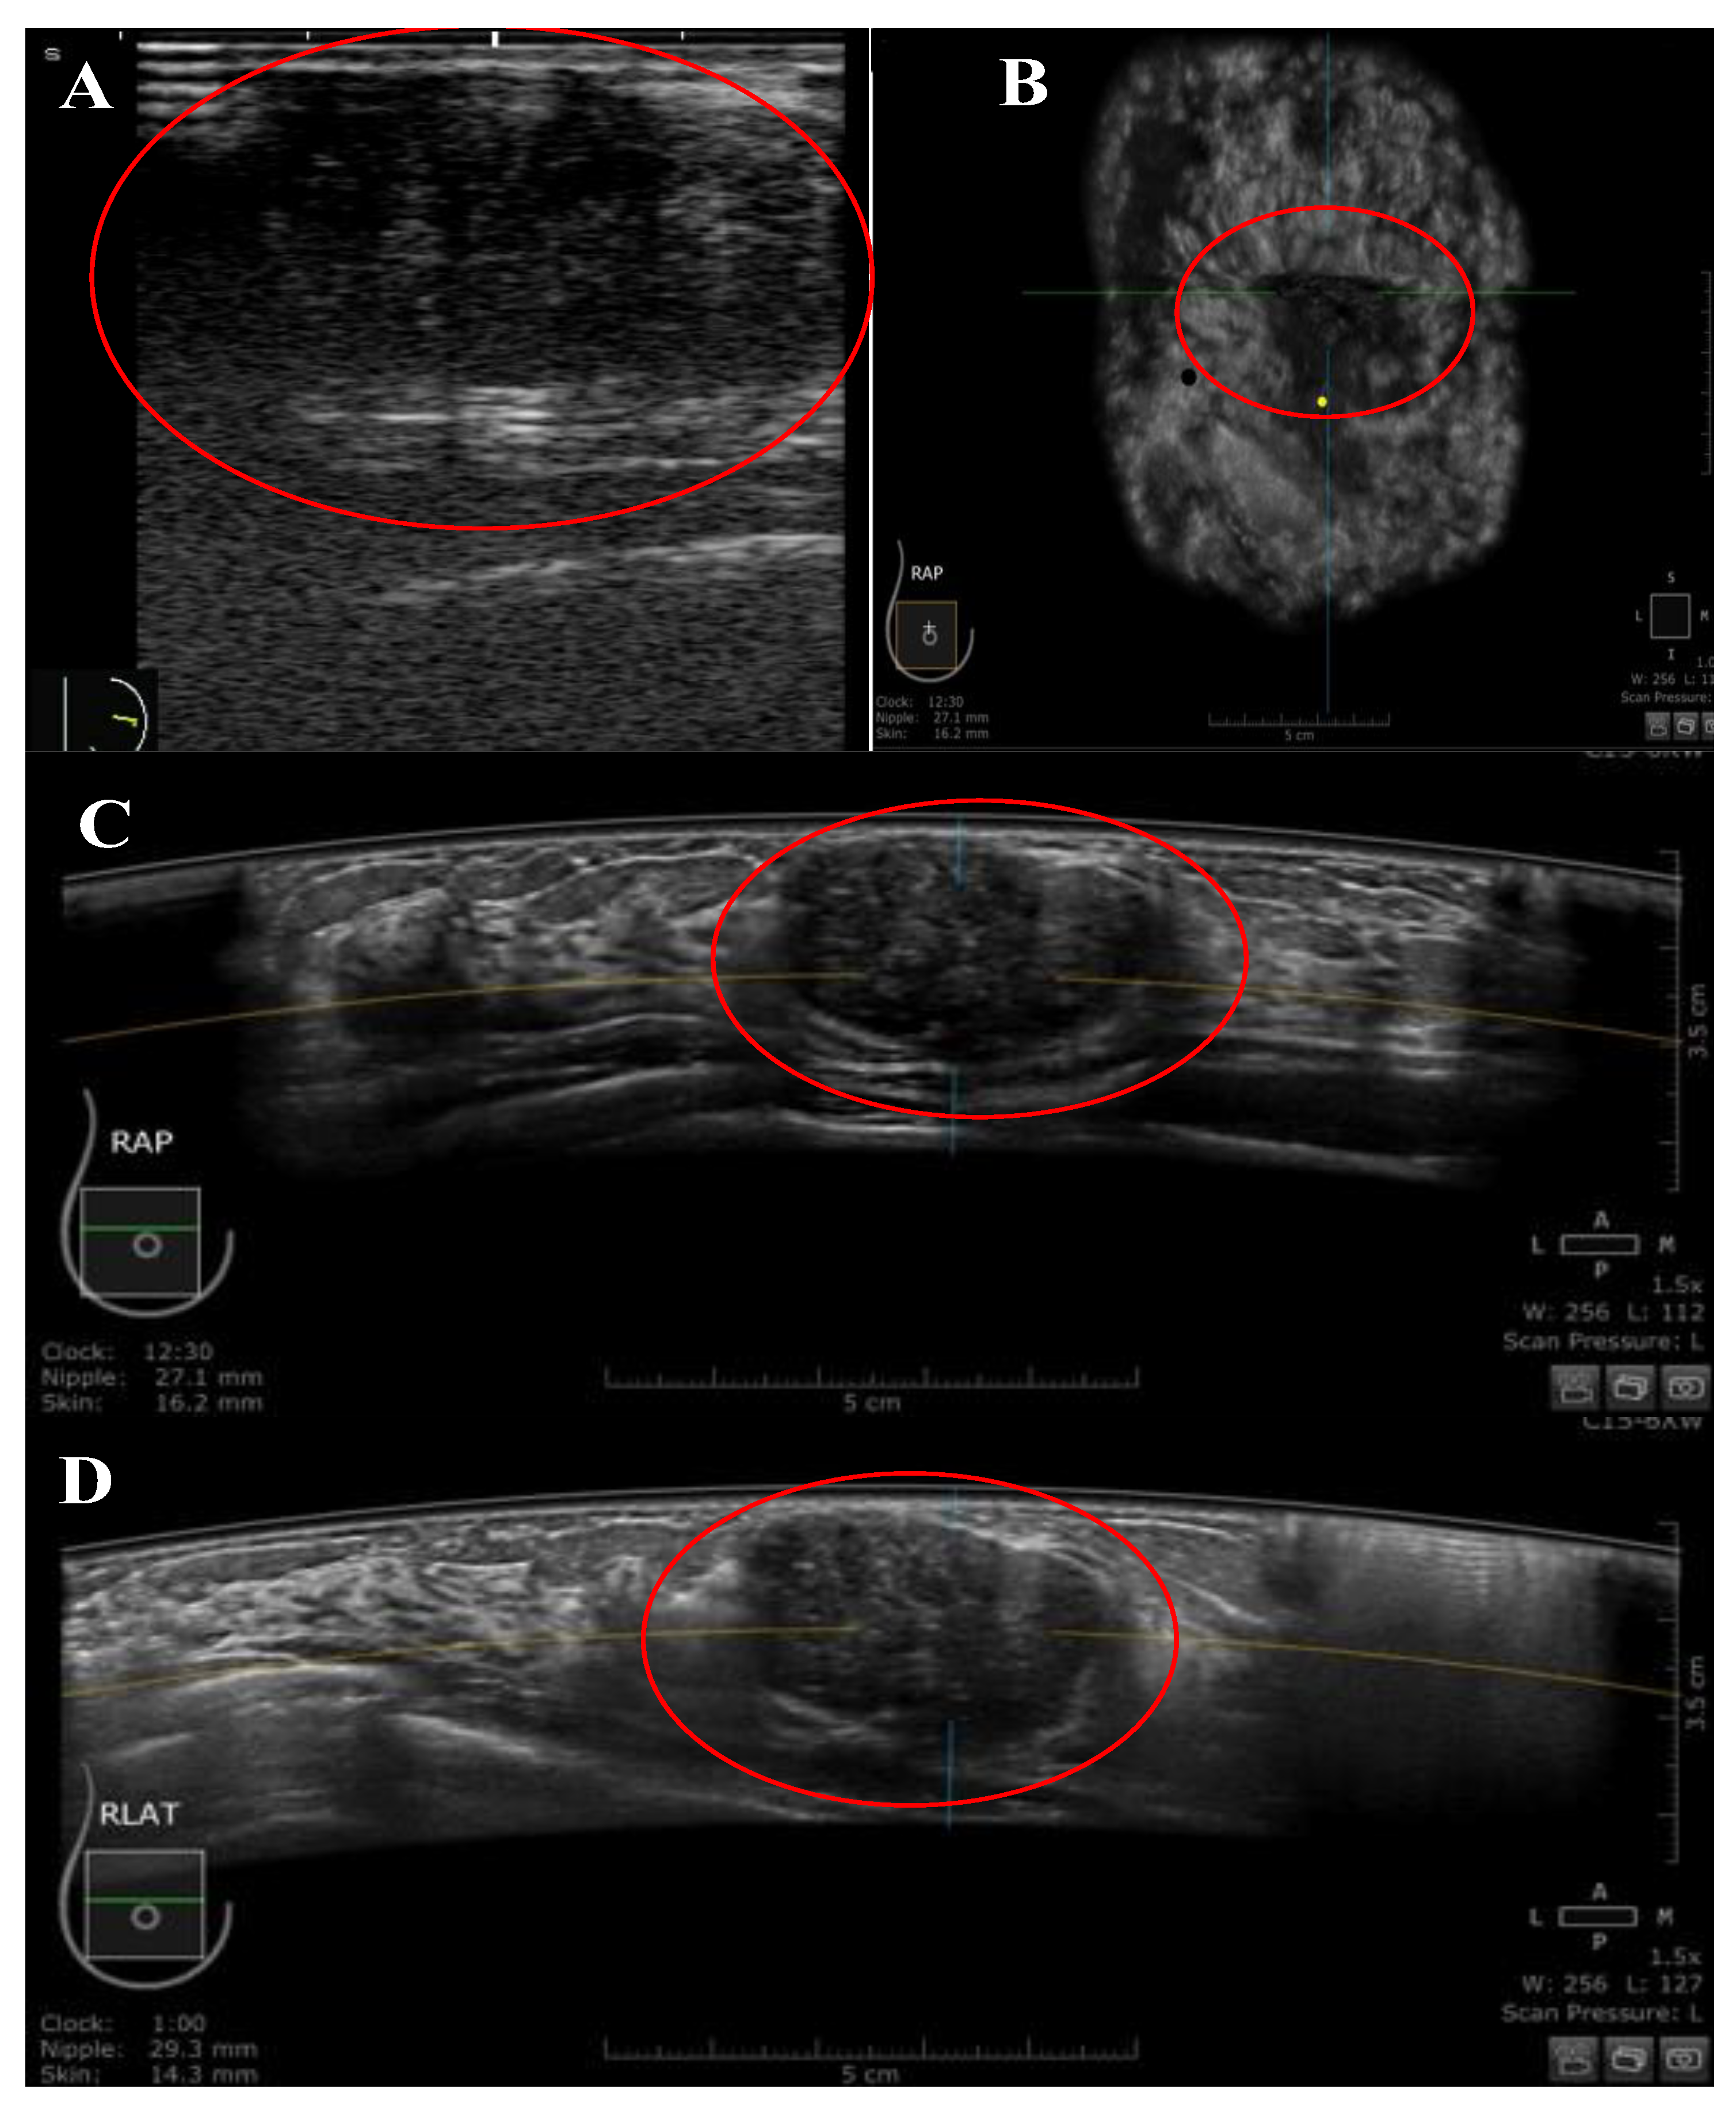

Figure 3.

A 29-year-old Malay female patient was presented with a right UIQ breast lump at a distance of 27.1 mm from the nipple. (A) Handheld US image showing an oval-shaped, hypoechoic, parallel mass, and heterogenous echo pattern with regular margins. The mass was classified as BIRADS category 3 by HHUS. (B–D) the mass was presented by ABUS in three orthogonal planes: coronal (B), transverse (C), and sagittal (D). The mass was classified as BIRADS category 3 by ABUS. The yellow dot marks the position of the nipple, and the red circle marks the lesion.